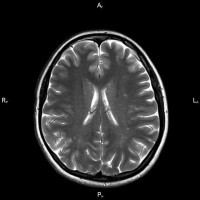

сотрясения головного мозга Дізнаємося про лікуванні струсу головного мозку , обговоримо симптоми цієї травми.